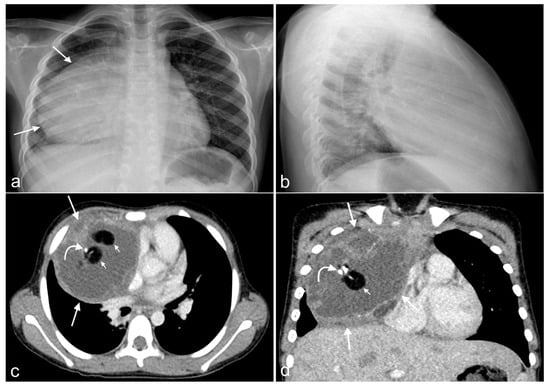

2.2. Radiology